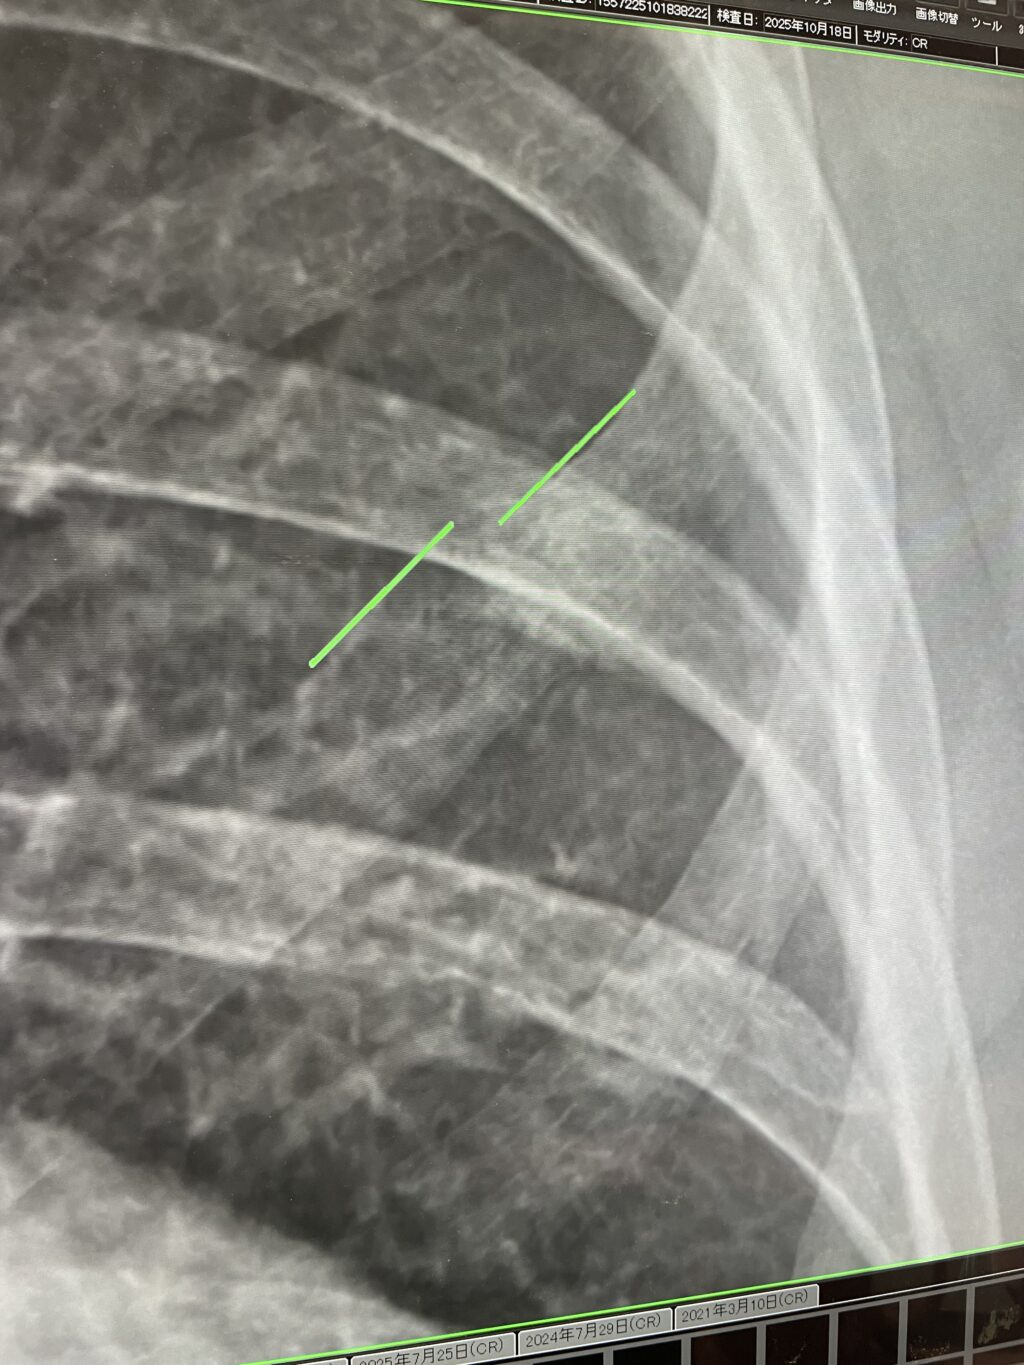

写真を並べて、先生もどこに骨折があるのかすぐには見分けられないくらいの状態にはなっていて、かなり順調のようでした。ちょっと今までとは撮影角度が変わっていたようで分かりにくいのですが…。

後ろから撮影しているから奥の方に見える写り型かたになるんですけど、やっぱり少し前の方なんですかね。もう感じられなくはなっているものの、骨折直後に激しい圧痛があった箇所で間違いないようです。骨がズレちゃっているのはハッキリ分かるとはいえ、レントゲン写真から骨折箇所が特定しにくくなっているので、かなり順調とのことでした。ということで経過観察はここまでで、どうしても気になるようだったら来月中旬にもう一回レントゲン撮影しよう、という話でした。ということは11月中旬くらいにはもうほぼ治っていると考えて間違いがないということのようです。